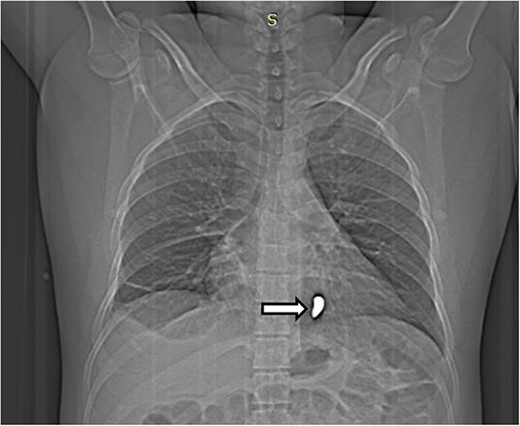

The complete blood count showed white cell count of 4300 cells, hemoglobin of 18.7 g/dl, and platelet of 285 000. Serum electrolyte, albumin and liver function tests were within normal range and creatinine was 1.19 mg/dl. Chest X ray showed bullet left of the sternum within the inferior aspect of the cardiac silhouette. Contrast CT scan detected minimal bilateral pleural collection with right basal segment atelectasis with 2.3 × 1.1 cm metallic density foreign body in the mediastinum located over the inferior border of ventricular wall (Figs 1–3). Troponin was 432.4 ng/ml. Electrocardiography showed V2 lead ST segment elevation. All the other leads were normal. The patient had three echocardiographs done, and only one showed the presence of foreign body within the myocardium of the left ventricle. Otherwise, no wall motion abnormality, or any sign of heart failure was detected.

Scout image of the chest showing a radio-opaque foreign body in the left side of the chest (white arrow).